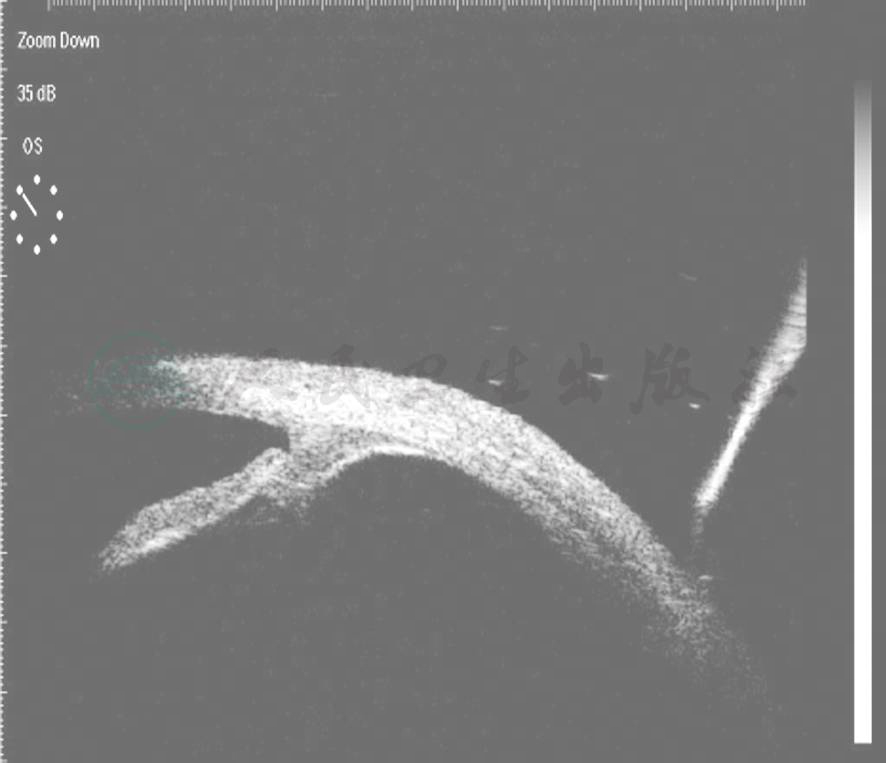

外伤性前房积血相关的眼球前段改变最重要的是前房角后退(recession of anterior chamber angle),一般发生于挫伤所致的闭合性眼外伤,表现为睫状肌纵行肌和环形肌之间分离(图4)。前房角后退的范围与前房积血的量或急性眼压升高并不一定相关。前房角后退发生前房积血者占30%~85%,早期或后期出现的青光眼与此有关。较广泛的前房角后退常伴有高发生率的迟发性青光眼,前房积血患者有6%~10%发生前房角后退性青光眼。睫状体从巩膜突上分离造成睫状体断离,很少发生前房积血,而睫状体断离是低眼压的重要原因。

图4UBM示前房角后退